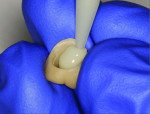

Two weeks later, the patient presented for a try-in of the final restoration, at which time a hemostat was used to remove the temporary crown (Figure 1). To completely remove the residual cement, pumice was used in a prophy cup to thoroughly clean the area (Figure 2). The try-in of the restoration entailed checking for marginal integrity, proper interproximal contacts, and an ideal occlusal relationship (Figure 3). Following this, all necessary adjustments were made utilizing a fine diamond football-shaped bur (285.5Z-TSZtech, Premier Dental).